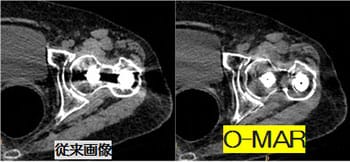

全く新しい画像再構成法O-MAR(Metal Artifact Reduction for Orthopedic implants)により、金属による画像への影響を抑制した診断に有用な画像を迅速に提供します。